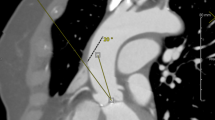

The ascending aorta is positioned to the right (more than halfway to the right of the right sternal border) at the level of the main pulmonary artery.

The distance between the ascending aorta and the sternum must not exceed 10 cm, and the α angle (the angle formed between the midline and the ascending aorta's inclination) should exceed 45°.